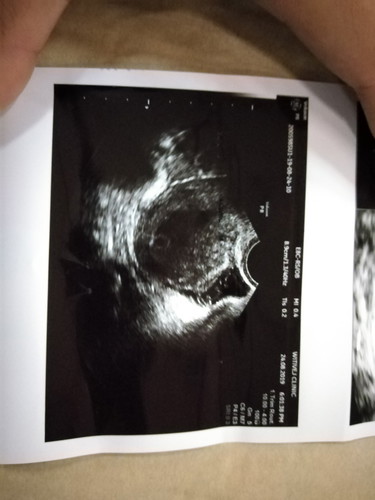

มีแม่ท่านไหนเจอปัญหาเหมือนเราไหม วันนี้เราตั้งใจจะไปฝากครรภ์ แล้วหมออัลตร้าซาวให้หมอบอกว่าเจอไข่แดงแล้ว แต่ทำไมถุงตั้งครรภ์?์เล็กลง หมอเลยนัดซาวอีกทีอีก2 อาทิต แม่ๆทำอย่างไรบ้างค่ะ เรากังวลมากคะ

สู้ๆค่ะ